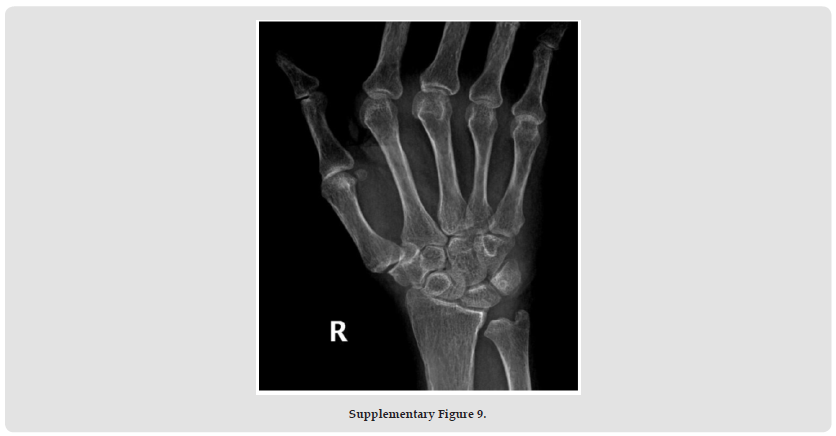

Psoriatic arthritis (PsA), a systemic autoimmune disease, manifests with remarkable clinical heterogeneity [1]. While axial involvement and peripheral joint destruction are well documented, the coexistence of severe spinal kyphosis and Mutilans-type arthropathy remains exceptionally rare. We present a diagnostically challenging case with concurrent progressive spinal deformity and osteolytic features of Mutilans [2]. This case report describes the complex clinical presentation of a rare psoriatic arthritis (PsA) patient with severe kyphosis and mutilating arthritis. A 69-year-old woman with a 50- year history of psoriasis developed worsening skin symptoms and joint pain in 2019. She was treated with cyclosporine, ezicizumab and secukinumab, which resulted in partial relief of skin symptoms but progressive joint destruction. Over the past two years, he had developed a complex sagittal and coronal spinal deformity (thoracolumbar kyphosis with scoliosis), accompanied by characteristic “telescopic” phalangolysis and ulnar deviation of the right hand. His serum markers (RF, anti-CCP, etc.) were normal. Imaging showed the coexistence of heterotopic ossification and osteolysis, consistent with the diagnosis of residual PsA combined with spinal PsA. The clinical significance of this case is that it highlights three key issues. Firstly, rapidly progressive spinal lesions can occur in the absence of a typical serological marker (negative HLA-B27); secondly, biological agents can cause separation of skin and joint effects.

Third, mechanical stress may accelerate the progression of spinal deformity in susceptible individuals. This suggests that dynamic monitoring of the spine in PsA patients should be intensified, especially in patients with long-term good skin control but new axial symptoms, and the evaluation strategy should be adjusted. Future research needs to further explore the mechanical-inflammatory interaction mechanism and establish precise treatment pathways for different clinical phenotypes. This case provides an important clinical demonstration to recognise the heterogeneity of PsA and the complexity of treatment (Supplementary Figures 1-11).